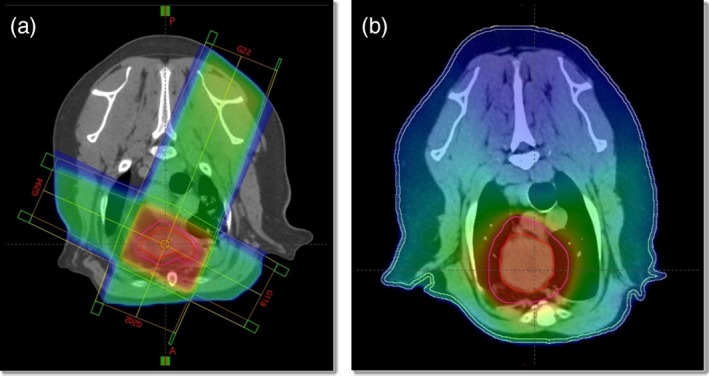

Canine cardiac hemangiosarcoma (cHSA) represents a complex clinical challenge in that those afflicted have an acute risk of death due to cardiac tamponade and high morbidity and mortality given the frequency of metastasis. Previous studies show that radiation therapy (RT) can decrease the risk of tamponade; however, an optimal approach has yet to be determined. The objective of this study was to evaluate the outcomes of dogs with presumptive cHSA treated with varied RT protocols and modalities, and to contrast findings with previously published literature. Secondary objectives were to assess differences in outcomes between those that received chemotherapy post-RT or did not, single fraction versus multiple-fraction RT protocols, and CT-guided versus manually calculated treatment plans. Twenty-seven dogs with echocardiographic evidence of an atrial or auricular cardiac mass that received RT were included. The frequency of pericardiocentesis before and post-RT were compared. Overall survival time was determined, along with survival time specific to those that received chemotherapy, were treated with CT-based radiation plans, and were prescribed a single fraction versus multiple fractions. Pericardiocentesis was performed an average of 1.1 times per week before RT, and an average of 0.18 times per week after RT (p = 0.01). Median overall survival time was 137 days. Plans made without CT guidance were associated with more adverse radiation events, but all were minimally impactful on quality of life. Most dogs died or were euthanized due to metastatic disease. This study shows similar benefits to previously published data in a larger cohort of dogs using a less-conformal radiation modality. As well, it highlights future directions to identify optimal systemic therapies to delay the onset of metastasis.